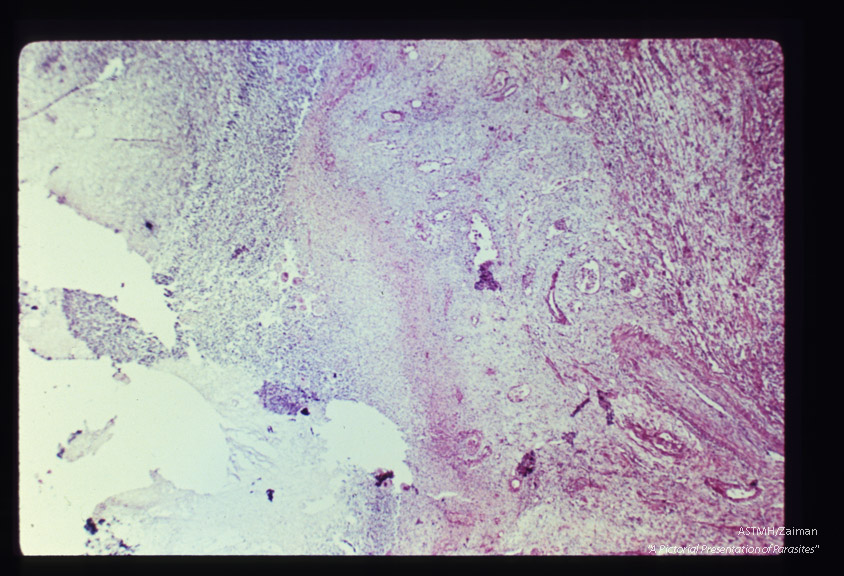

Low and high powered views of trophozoites within inflamed appendix. (H&E).

Balantidium coli

Description: Low and high powered views of trophozoites within inflamed appendix. (H&E).